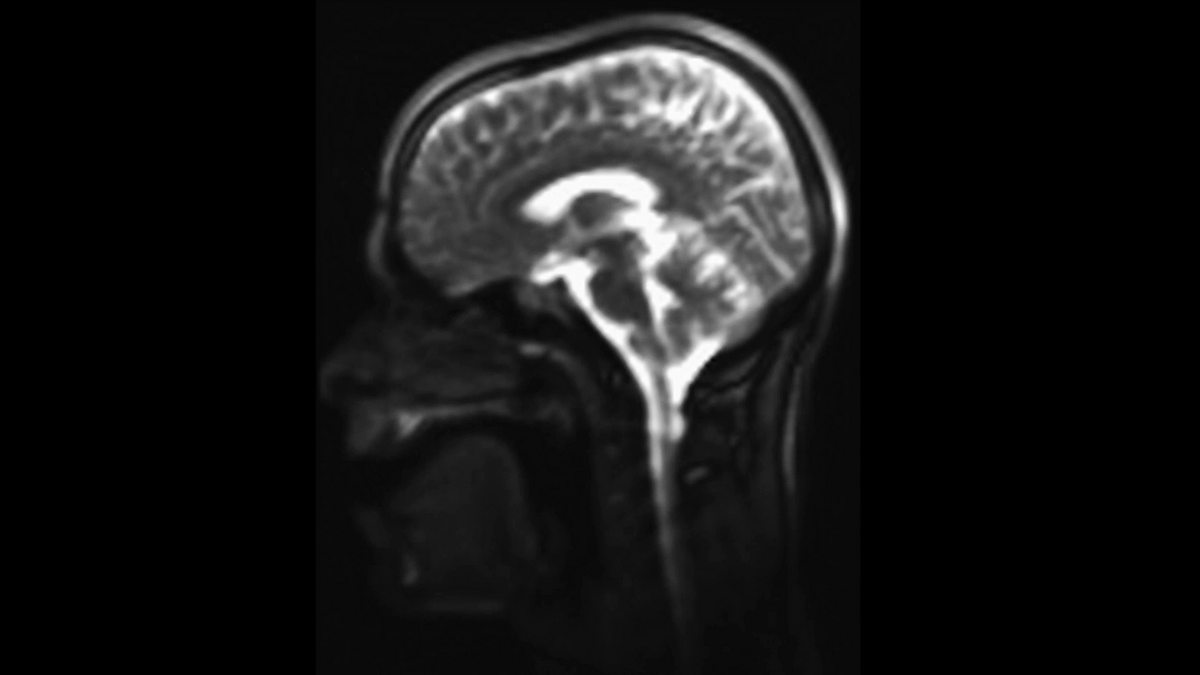

Take a look inside Alex Lathbridge’s vocal cords during a rap performance. This moving MRI scan was created by neuroscientist Sophie Scott and her team from University College London.